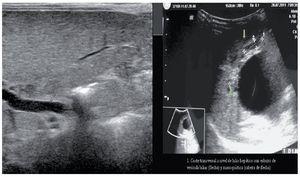

The AUS showed morphologic alterations in the extrahepatic biliary tract: case 4, fibrous cord replacing the bile duct (Fig. 2); neither the gallbladder nor the bile duct were detected in case 1 (Fig. 3); case 3 presented with a choledochal cyst and a suggestion of a gallbladder, and the histopathologic study showed fibrosis at the level of the porta hepatis, where there should be a lumen at the origin of the common bile duct. Intraoperative cholangiography was carried out in 3 of the 4 patients and there was contrast medium extravasation when it was injected into the remnant of the extrahepatic biliary tract. Intraoperative cholangiography was not done in the patient presenting with the choledochal cyst; diagnosis was established by the macroscopic study of the biliary tract that revealed the pouch and microscopic study showed it was associated with hepatitis.

Figure 2. Case 4 at 19 days of life. Liver and biliary tree ultrasound taken in the city of birth, identifying a fibrous cord above the porta hepatis that would normally correspond to the common bile duct with an interior lumen.

Figure 3. Panel A. Case 1. Absence of the gallbladder and bile duct. Panel B. Case 3. Transversal view at the level of the hepatic hilum. The gallbladder and a cystic mass are suggested (arrowhead).